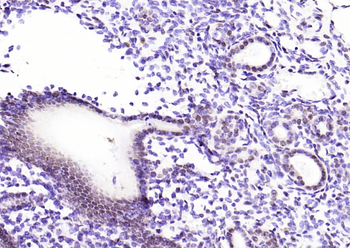

CDKN1A Antibody

Catalog Number: orb682382

| Description | CDKN1A Antibody |

| Target | CDKN1A |